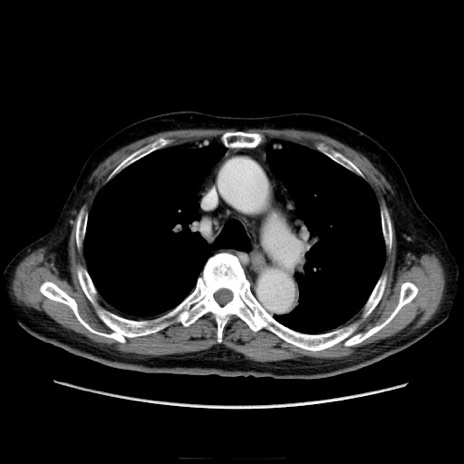

症例21(横断像)

【症例】70歳代男性

【主訴】腹痛

【現病歴】肝硬変・肝細胞癌にてかかりつけの方。約9時間前に食後より腹痛出現。症状が徐々に増悪し、嘔吐出現したため来院。

【既往歴】肝硬変、肝細胞癌(RFA、TACE後)

【身体所見】意識清明、表情苦悶様、BT 36℃、BP 129/78mmHg、P 88bpm、SpO2 97%(RA)、右上腹部から心窩部にかけて圧痛あり、反跳痛なし、筋性防御あり。

【データ】WBC 5800、CRP 0.16